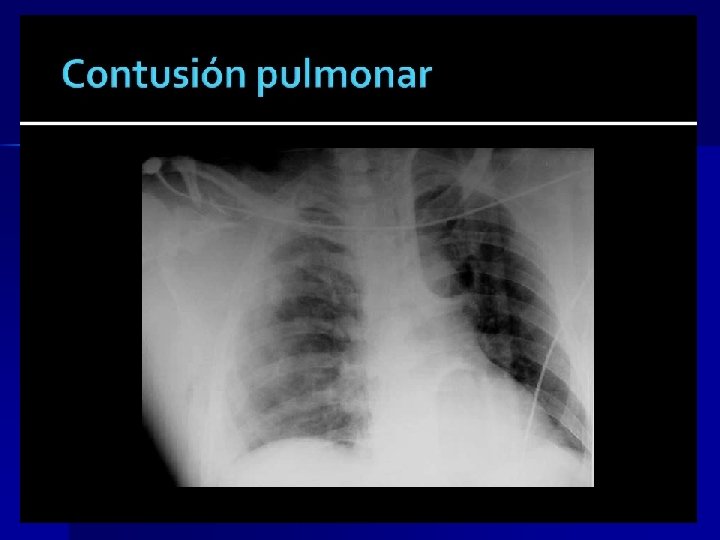

Rx TÓRAX Hemotórax: -Opacificación sello tórax -Sangrado de inicio > 1500 cc toracotomía -Sangrado es de 200 -300 cc/h toracotomía n Contusión pulmonar: -Patrón irregular intersticial -Disnea leve a Distress Respiratorio del Adulto -Magnitud puede no verse al inicio -Gases arteriales y Rx tórax seriadas (c/6 hrs) n